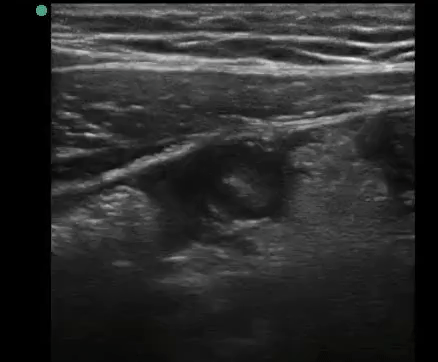

Point of care transvaginal ultrasound showed the following:

A tubular structure was visualized in the right lower quadrant. Cross sectional diameter measured 11.5 mm.

Structure was non-peristalsing, non-compressible and was hyperemic vascular flow as shown above